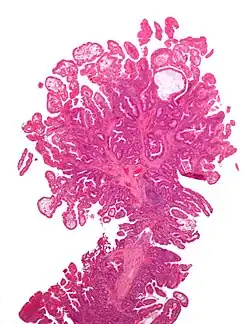

| Hyperplastic polyp | 0% | No dysplasia.[10]

|

| |

| Tubular adenoma | 2% at 1.5 cm[12] | Low to high grade dysplasia[13] | Over 75% of volume has tubular appearance.[14] |

| Tubulovillous adenoma | 20% to 25%[15] | 25–75% villous[14] |

| Villous adenoma | 15%[16] to 40%[15] | Over 75% villous[14] |

Hyperplastic polyp

Most hyperplastic polyps are found in the distal colon and rectum.[18] They have no malignant potential,[18] which means that they are no more likely than normal tissue to eventually become a cancer.